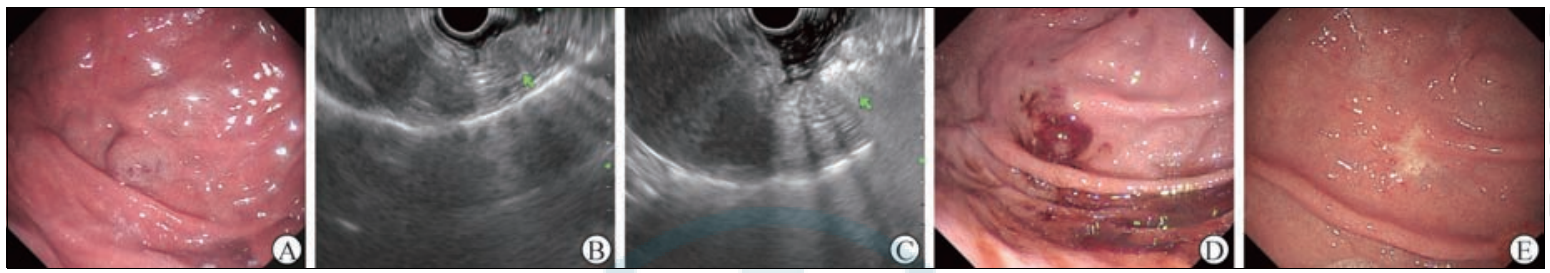

入院后行血常规、粪便常规、粪便隐血试验、肝功能、肿瘤标志物等检查,均未见明显异常。2022 年6 月21 日肝脏CT增强检查提示,胃底部见一直径约12mm的结节影,动脉期未见明显强化,门静脉期明显不均匀强化,考虑良性病变(图1)。2022年6月23日内镜检查提示胃底大弯侧黏膜下蓝紫色血管样隆起簇和明显结节状隆起,较大隆起结节直径约10 mm,考虑为胃底血管瘤(图2A、2B);换用纵轴超声内镜进镜,扫描隆起结节状病灶处见蜂窝状低回声团块,起源于黏膜下层(图2C),测量大小为9. 1 mm × 11 mm,彩色多普勒超声血流图像显示少量的血流信号;遂超声内镜引导选用22G注射针(南微医学科技股份有限公司)刺入病灶处,并向内注射聚桂醇约10 mL(图2D);注射后再次用超声内镜扫描发现术后病灶处腔内高回声充填,黏膜下隆起明显塌陷(图2E)。术后嘱患者常规禁食12h,予以补液、护胃、头孢呋辛预防性抗感染等对症支持治疗,术后未出现发热、腹胀、腹痛、呕血、黑便等症状,术后第2 天顺利出院。2022 年11月3日患者入院复查,内镜下仍见胃底大弯侧黏膜下血管样结节隆起,较上一次内镜检查范围明显缩小(图3A),遂再次行超声内镜引导聚桂醇消融术(图3B、3C),术后血管瘤腔内呈高回声充填,病灶较前注射前明显塌陷(图3D)。术后住院观察期间患者未出现发热、呕血、黑便、腹胀、腹痛等情况,术后第2天顺利出院。3个月后(2023年2月9日)患者再次复查,内镜下见胃底大弯侧黏膜瘢痕样改变,注水后用12 MHz超声微探头扫描见原病灶处胃壁层次结构正常(图3E)。目前患者门诊定期随访中,至截稿一般情况良好。

图3 2022年11月3日第2次超声内镜引导聚桂醇消融术治疗胃血管瘤过程及3个月后(2023年2月9日)的复查结果A 2022年11月3日复查内镜示胃底血管样病变范围较6月23日内镜检查缩减B 2022年11月3日二次行纵轴超声内镜扫描示病灶为位于黏膜下层低回声团块(箭头所示) C 2022年11月3日二次行超声内镜引导向胃血管瘤病灶注射聚桂醇后病灶腔内呈高回声充填(箭头所示) D二次治疗后病灶明显塌陷E二次治疗3个月后复查内镜见胃底瘢痕样改变,未见血管瘤样病变